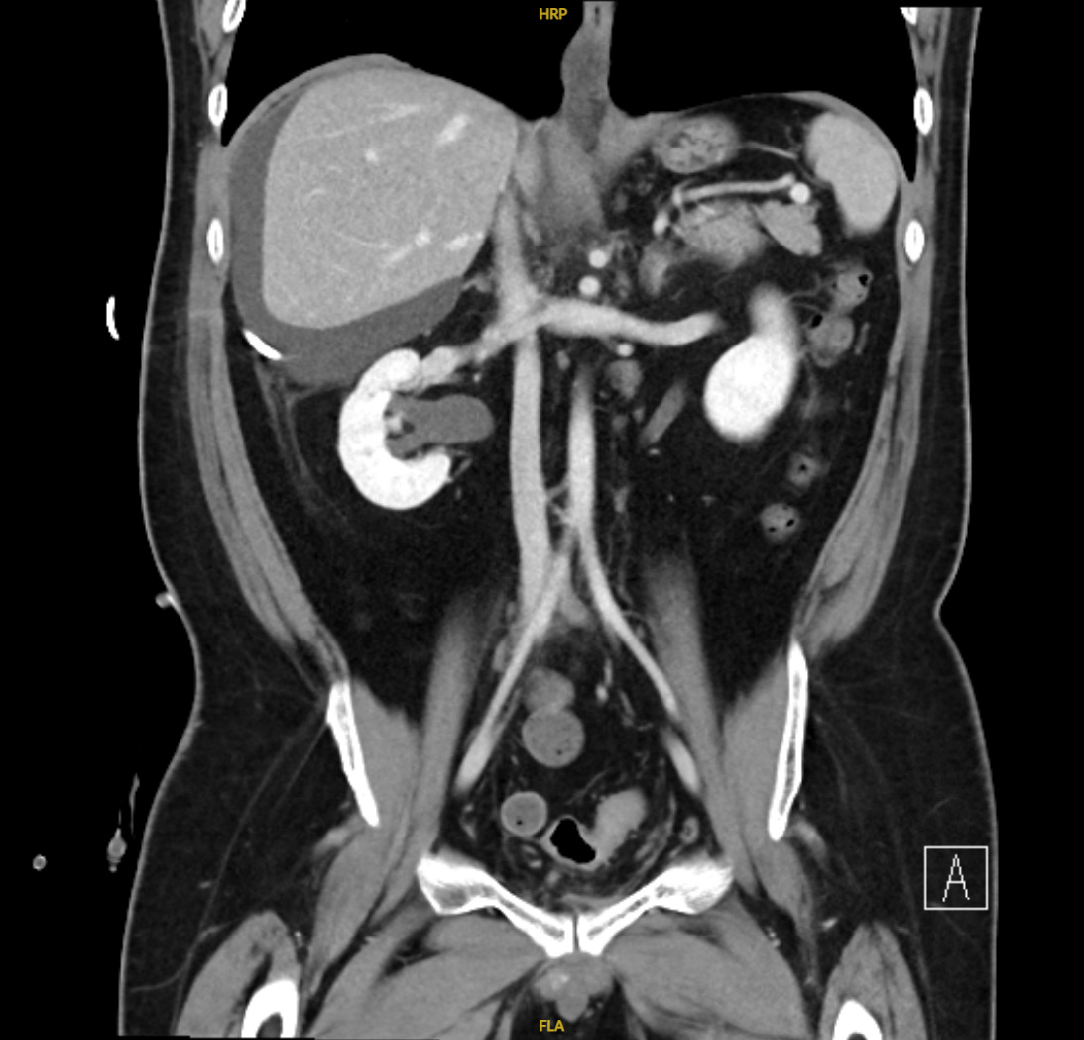

Figure 3 Interval imaging with drain in situ.